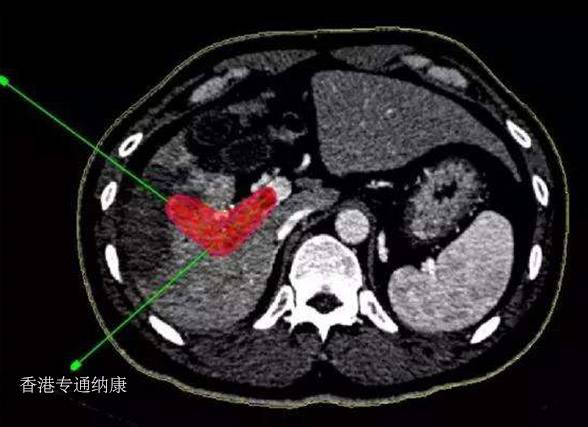

二、DS8201(Enhertu)安全性及副作用

在DS8201的大部分临床研究中,观测到3级以上不良反应和间质性肺炎的概率比较高,这是其他Her2-ADC药物中不多见的。

比如在DS8201的一项代号为DS-Gastric-01的研究中,3级以上不良反应发生率高达85.6%,有12.8%的患者接受治疗后发生间质性肺炎,并出现1例与间质性肺炎相关的死亡事件。

间质性肺炎是因为肺间质纤维化或者肺泡炎等导致的一种疾病,分为急性和慢性两种,急性间质性肺炎如果治疗不及时,致死率非常高。

对于这种现象,业界有分析认为,肺泡巨噬细胞富集组织蛋白酶B,这种酶对DS8201的连接子有裂解作用,可能导致小分子毒素提前释放,进而导致肺毒性。